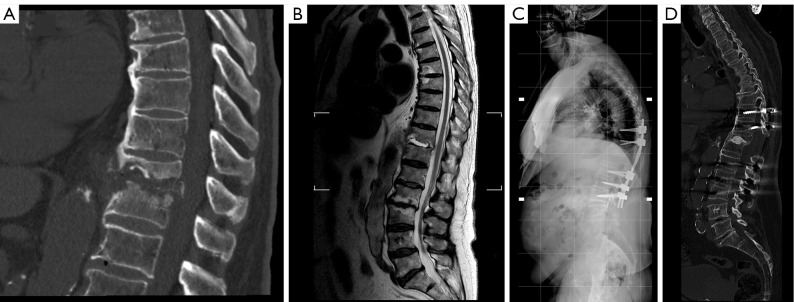

The article aims to describe the novel surgical technique of filling anterior spine cavitations in pyogenic spondylodiscitis (PS) using bioactive glass S53P4 (BAG-S53P4) (BonAlive®) in association with posterior spinal stabilization alone and its results in the first three patients. The technique starts with a posterior approach and instrumentation of the spine, total or partial laminectomy (when needed), debridement of the intervertebral space and cavity filling with BAG-S53P4, without any additional anterior instrumentation (i.e., meshes/cages). We retrospectively reviewed the first three cases of spondylodiscitis surgically treated with this technique at the department of orthopaedic surgery of the ASST-Ovest Milanese, Legnano Hospital (Italy). Functional outcomes, pain level, and C-reactive protein (CRP) trends were reported. Serial plain radiographs were collected, and a computed tomography (CT) scan was performed after a period of 2-3 years. A rapid improvement and healing from infection were observed in all cases with progressive spinal fusion and restoration of the previous quality of life. We did not observe major adverse events. BAG-S53P4 can be safely introduced in the disk space through a posterior approach to fill vertebral cavitation when the posterior wall is almost intact. It may be considered a safe and useful biomaterial in the surgical treatment of spondylodiscitis, helping in the eradication of the infection and promoting progressive spinal fusion. With this technique, anterior instrumentation and double approaches could be avoided in case of limited bone defects and moderate spinal deformity.

Abstract Image